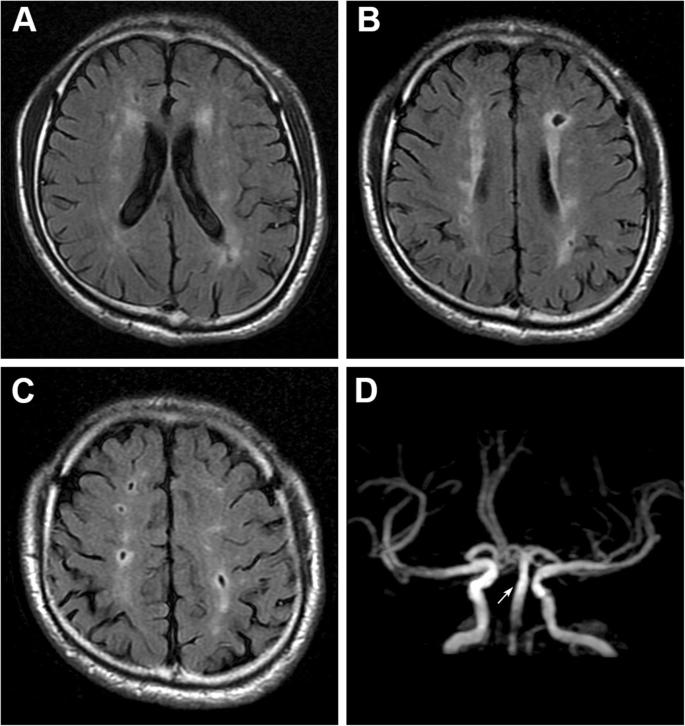

二、无症状的腔梗。

如果出现腔隙性脑梗死该怎么办呢?

但是如果没什么表现,仅仅是在体检或者在检查其他疾病的过程中发现有腔梗,这个时候该怎么办呢?

临床当中这种情况是很常见的,我们称为无症状的腔隙性脑梗死,针对这类患者,请您别害怕。

虽然我们称之为脑梗死,但他对我们的危害并不大,只需要改善生活方式,积极预防下一次腔梗就可以了。

四、脑白质脱髓鞘。

面对一份头部的CT报告单,最常见的字眼其实就是脑白质脱髓鞘了,针对这种问题该怎么解决呢?

其实针对大多数患者来说,并不需要解决。

看上去脑白,质脱髓鞘是一种疾病,可是实际上只要岁数到了,或多或少都会有这种情况,轻度的脑白质脱髓鞘在55岁以上的人群当中其实是很常见的。

当然,很多人虽然有脑白质脱髓鞘,但并没有什么症状也没有什么感觉。

针对这类患者其实并不需要治疗,症状较轻的时候也没有什么好的治疗方式可以改善,最重要的就是强调改善生活方式,把自己大脑子的态势调整好。

但是要小心,如果是非常严重的脑白质脱髓鞘可能就是一种疾病了,我们也应该好好的治疗,比如脑神经炎,而且出现头痛。